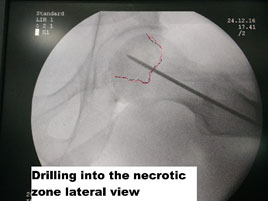

Core decompression

This technique involves the drilling of the femoral head with a drill hole, thereby reducing the intraosseous pressure. This reduction of pressure helps to maintain the remaining blood flow and thus improves the outcome. It is advocated in the pre-collapse phase, and once collapse starts, there is a minimal benefit for core decompression. The success rate of this technique reamed from 30-60%based on the method and the study

24 Year old male presents with early pre-collapse AVN of the hip joint, was treated by core decompression and BMAC (Bone Marrow Aspirate Concentrate).

In our practice,- we follow the technique of core decompression, debridement of avascular bone with a burr, augmentation with stem cells harvested from the patient himself with precision radiological guidance. If a patient understands the cost-benefit implications of BMP usage, we use it along with allograft substitutes. This “modified cocktail therapy” where a patient undergoes surgical debridement and immediate augmentation along with medication and ESWT help’s in giving the best chance to avoid joint replacement surgery.